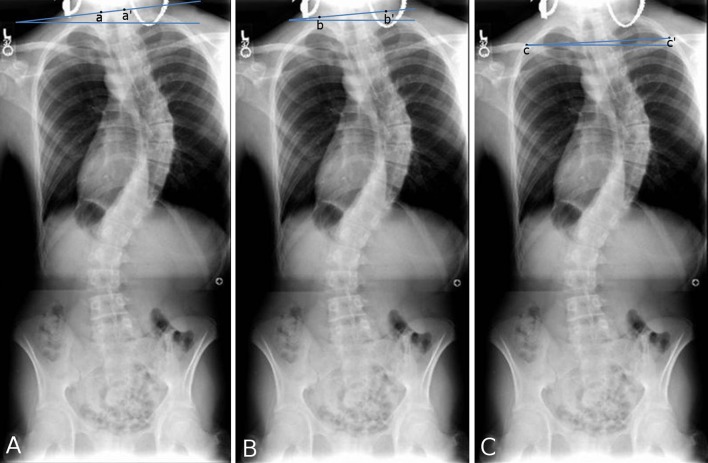

Fig. 1.

Schematic of radiographic measurements. a T1 tilt angle (a–a′ and horizontal line), b first rib angle (b–b′ and horizontal line), c clavicle rib intersection angle (c–c′ and horizontal line)